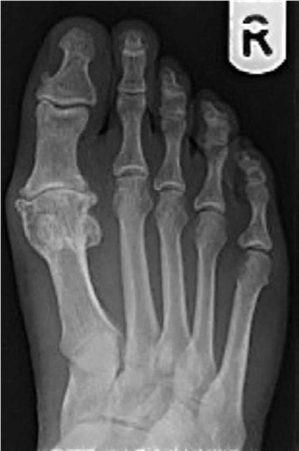

Foot and ankle structured oral questions7: Hallux rigidus EXAMINER : This 45-year-old male patient has presen…